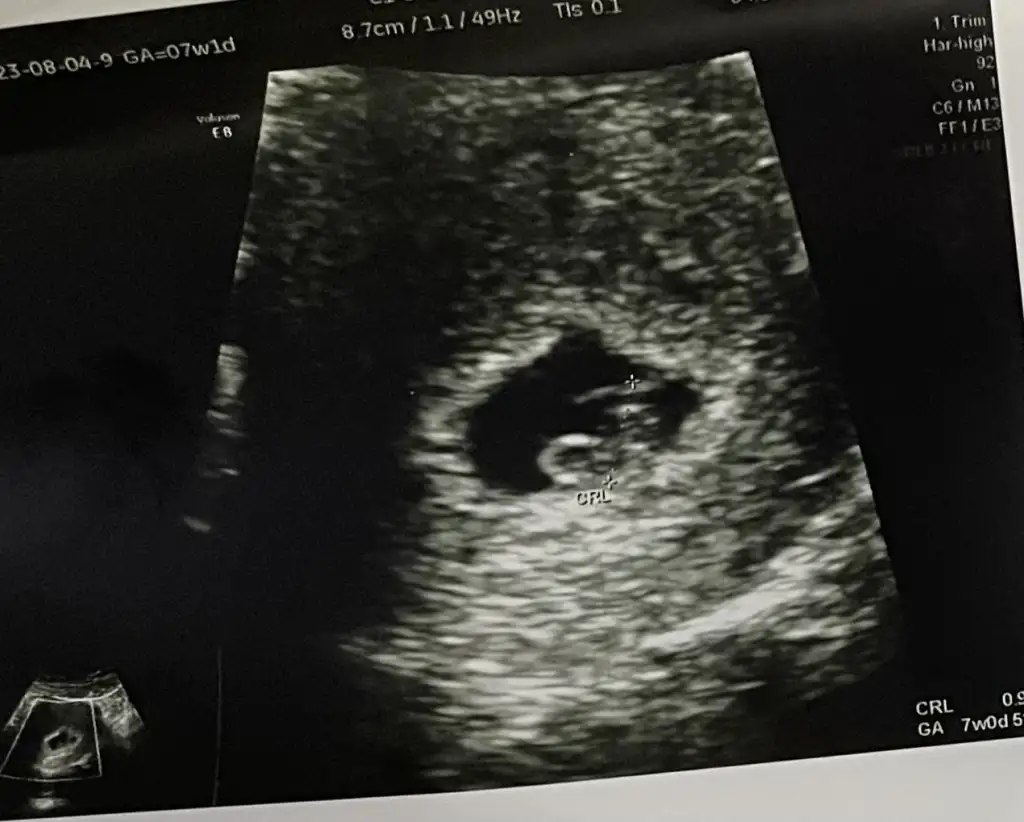

Banda bakarmisiniz karından 6+5 şimdiden Allah razı olsun